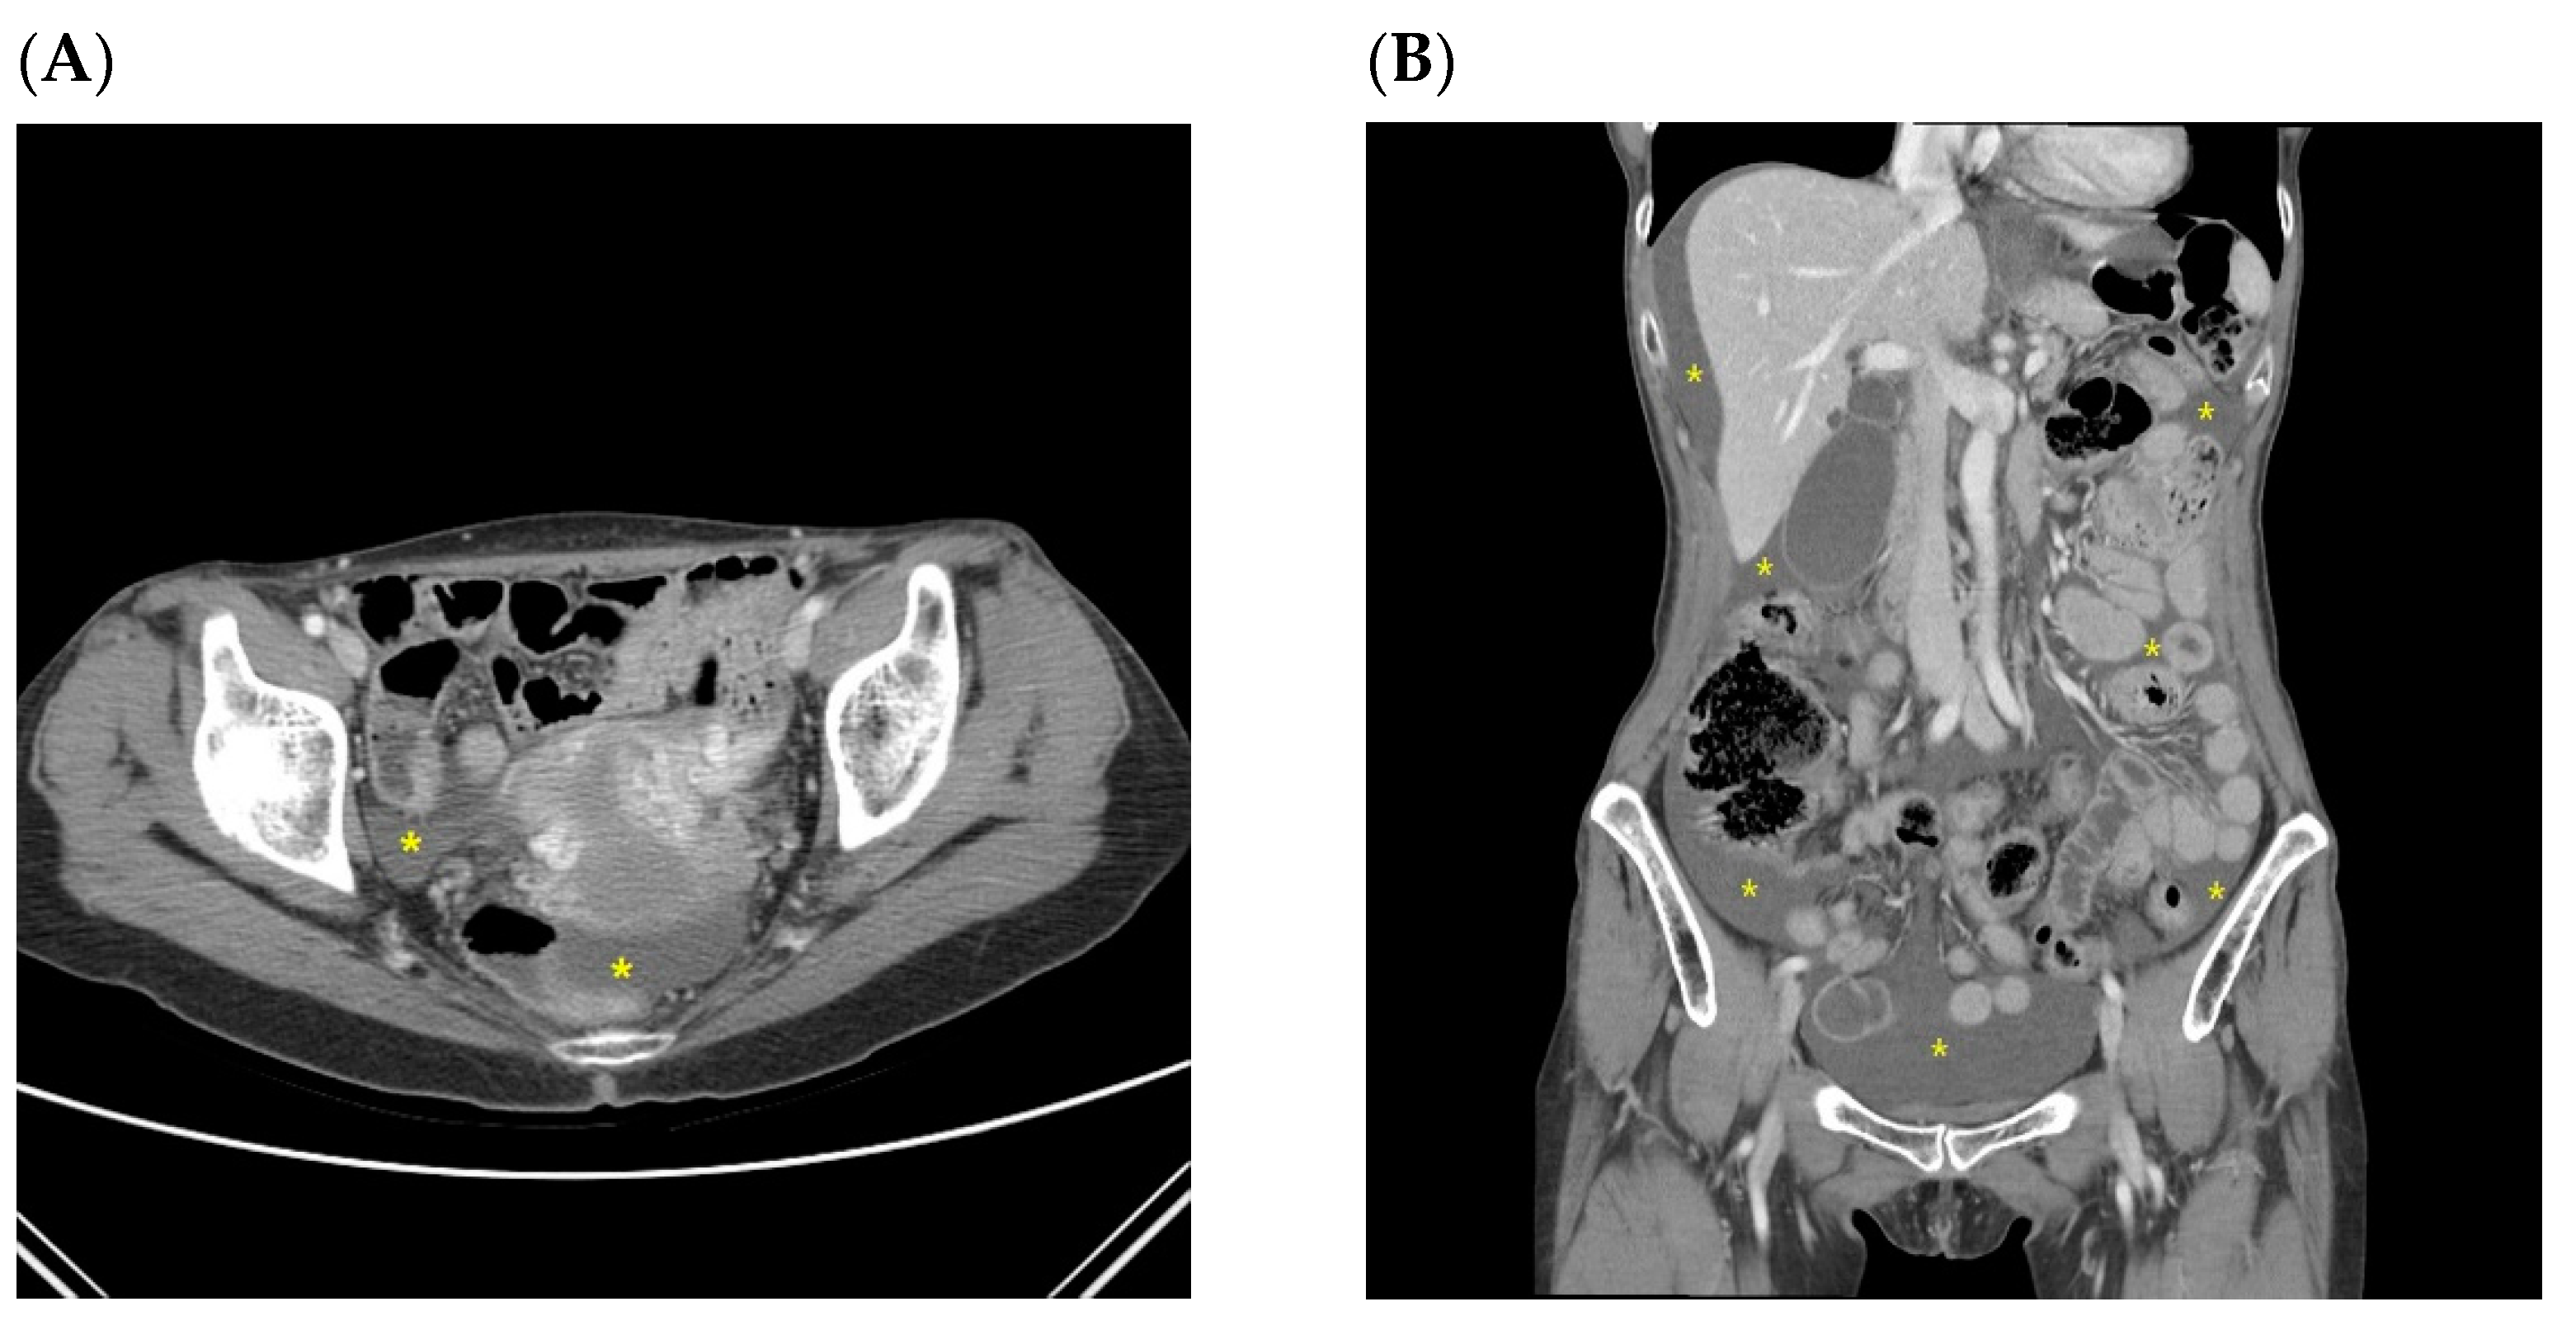

| Pt 1 | 65/M | PG | T3N3a | small pelvic cavity | Simultaneous with recurrence | T colon (increased ascites in the pelvic cavity) | 44.4 | 8.1 |

| Pt 2 | 53/F | TG | T4bN3b | small pelvic cavity | Simultaneous with recurrence | Peritoneum (increased ascites, peritoneal thickening, bowel obstruction, and Krukenberg tumors) | 18.2 | 13.2 |

| Pt 3 | 40/F | TG | T4aN3a | small pelvic cavity | Simultaneous with recurrence | Peritoneum (nodularity and increased ascites) | 73.2 | 70.3 |

| Pt 4 | 59/F | TG | T4aN3a | small pelvic cavity | Simultaneous with recurrence | Peritoneum (increased ascites and peritoneal thickening) | 25.2 | 21.7 |

| Pt 5 | 39/F | TG | T3N3b | small pelvic cavity | Simultaneous with recurrence | Peritoneum (Krukenberg tumors, nodularity, and increased ascites) | 12.1 | 9 |

| Pt 6 | 57/F | TG | T3N3a | small pelvic cavity | Simultaneous with recurrence | Peritoneum (bowel obstruction and increased ascites) | 9.8 | 4.4 |

| Pt 7 | 61/F | TG | T3N1 | small pelvic cavity | Simultaneous with recurrence | Peritoneum (increased ascites, T colon, and mesentery LNs) | 29.6 | 26 |

| Pt 8 | 68/F | PG | T4aN2 | small pelvic cavity | Simultaneous with recurrence | Peritoneum (increased ascites and peritoneal thickening) | 11.7 | 5.3 |

| A patient who first recurred with malignant ascites without other CT findings related to peritoneal seeding (later confirmed by cytology) (n = 1) | ||||||||

| Pt 9 | 49/F | TG | T3N3a | small pelvic cavity | ||||